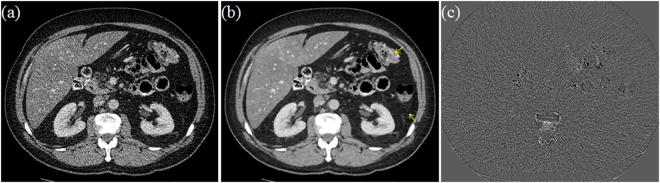

X-ray computed tomography (CT) has been widely used to provide patient-specific anatomical information in the forms of tissue attenuation. However, the cumulative radiation induced in CT scan has raised extensive concerns in recently years. How to maintain reconstruction image quality is a major challenge for low-dose CT (LDCT) imaging. Generally, LDCT imaging can be greatly improved by incorporating prior knowledge in some specific forms. A joint estimation framework termed discriminative prior-prior image constrained compressed sensing (DP-PICCS) reconstruction is proposed in this paper. This DP-PICCS algorithm utilizes discriminative prior knowledge via two feature dictionary constraints which built on atoms from the samples of tissue attenuation feature patches and noise-artifacts residual feature patches, respectively. Also, the prior image construction relies on a discriminative feature representation (DFR) processing by two feature dictionary. Its comparison to other competing methods through experiments on low-dose projections acquired from torso phantom simulation study and clinical abdomen study demonstrated that the DP-PICCS method achieved promising improvement in terms of the effectively-suppressed noise and the well-retained structures.

X 射线计算机断层扫描(CT)已广泛用于提供组织衰减形式的患者特定解剖信息。然而,近年来 CT 扫描引起的累积辐射引起了广泛关注。如何在保持重建图像质量是低剂量 CT(LDCT)成像的主要挑战。通常,可以通过以某些特定形式合并先验知识来大大改善 LDCT 成像。本文提出了一种称为鉴别先验-先验图像约束压缩感知(DP-PICCS)重建的联合估计框架。该 DP-PICCS 算法通过分别基于组织衰减特征补丁和噪声-伪影残差特征补丁的样本的原子构建的两个特征字典约束来利用鉴别先验知识。此外,通过对来自体模模拟研究和临床腹部研究的低剂量投影的实验,先验图像的构建依赖于两个特征字典的鉴别特征表示(DFR)处理。通过与其他竞争方法的比较,DP-PICCS 方法在有效抑制噪声和保留结构方面取得了有希望的改进。